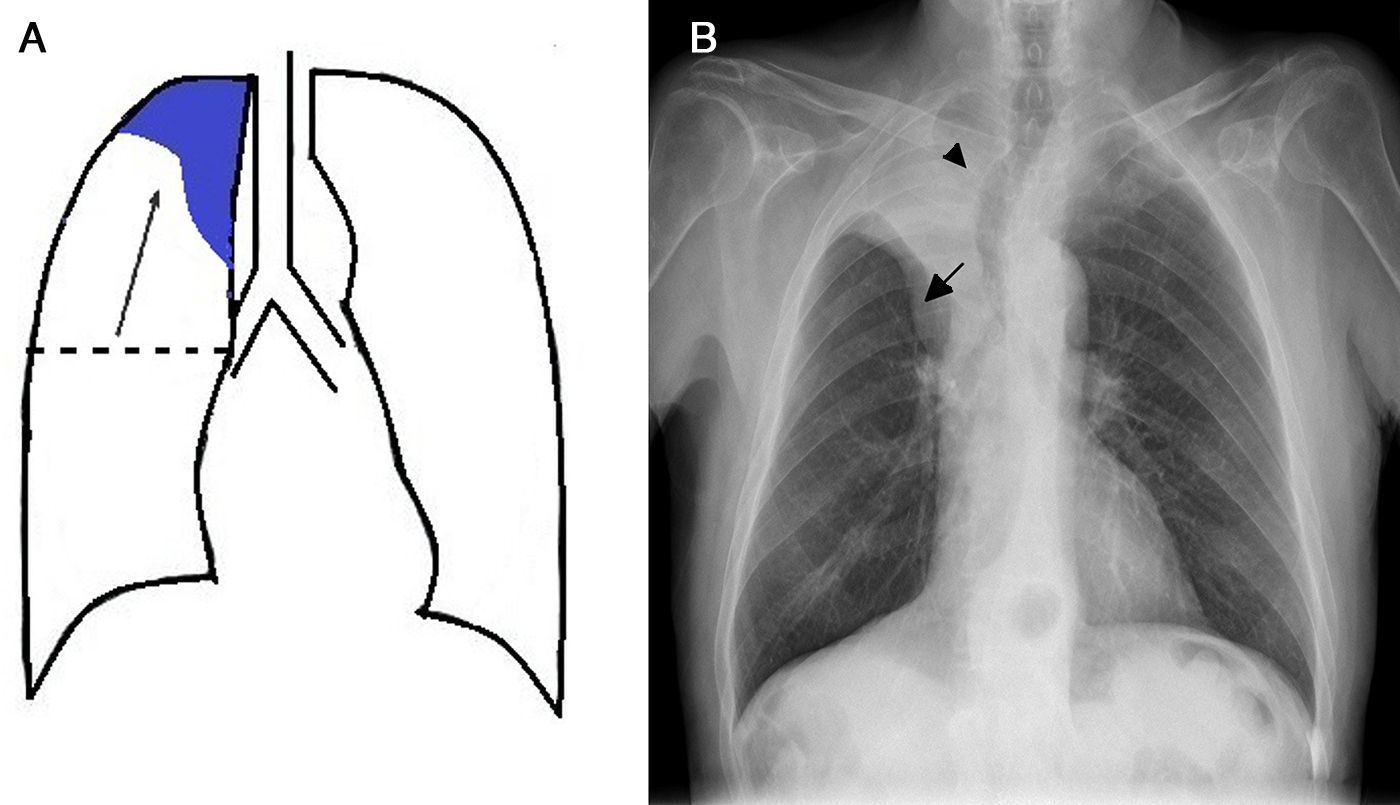

Atelectasis is an important indicator of potentially severe underlying disease that must be diagnosed as early as possible. One of the most common mechanisms is the reabsorption of air distal to respiratory tract obstruction. The chest X-ray is an excellent tool to diagnose atelectasis, and it is especially useful for ruling out central bronchial obstructions (e.g., from endobronchial tumors). If the signs of volume loss are not recognized correctly, the diagnosis and treatment can be delayed. This article describes the main findings of lobar atelectasis on chest X-rays and their correlations with CT findings, including the classic signs described in the literature and other, less known and sometimes subtle signs.